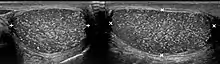

Testicular microlithiasis is an unusual condition diagnosed on testicular ultrasound. It is believed to be found in 0.1–0.6% of males globally, with frequency varying based on geographic location and is more often found in individuals with subfertility. It is a often an asymptomatic, non-progressive disease; though in a very small number of cases it may also cause bouts of extreme chronic fatigue, hormone imbalance and pain, which can be severe and accompanied by swelling around the testicular region (dependent on the size and location of the calcification). In an extremely rare select few cases, individuals with microlithiasis have also been known to experience calcification of the prostate, which can lead to the passing of stones. These rare cases can lead to secondary infections if not treated with care, due to the resulting damaged tissue. It is important to note however that these symptoms are rarely seen in the majority of people who have been diagnosed.

The cause is unknown, but this condition has been associated with testicular cancer in a small group of individuals, cryptorchidism, mumps, infertility and intraepithelial germ cell neoplasia. Classic testicular microlithiasis is defined as five or more echogenic foci per view in either or both testes, and limited testicular microlithiasis defined as one or more echogenic foci that do not satisfy the criteria for classic testicular microlithiasis. In 80% of cases, both testicles are affected.

Testicular ultrasound